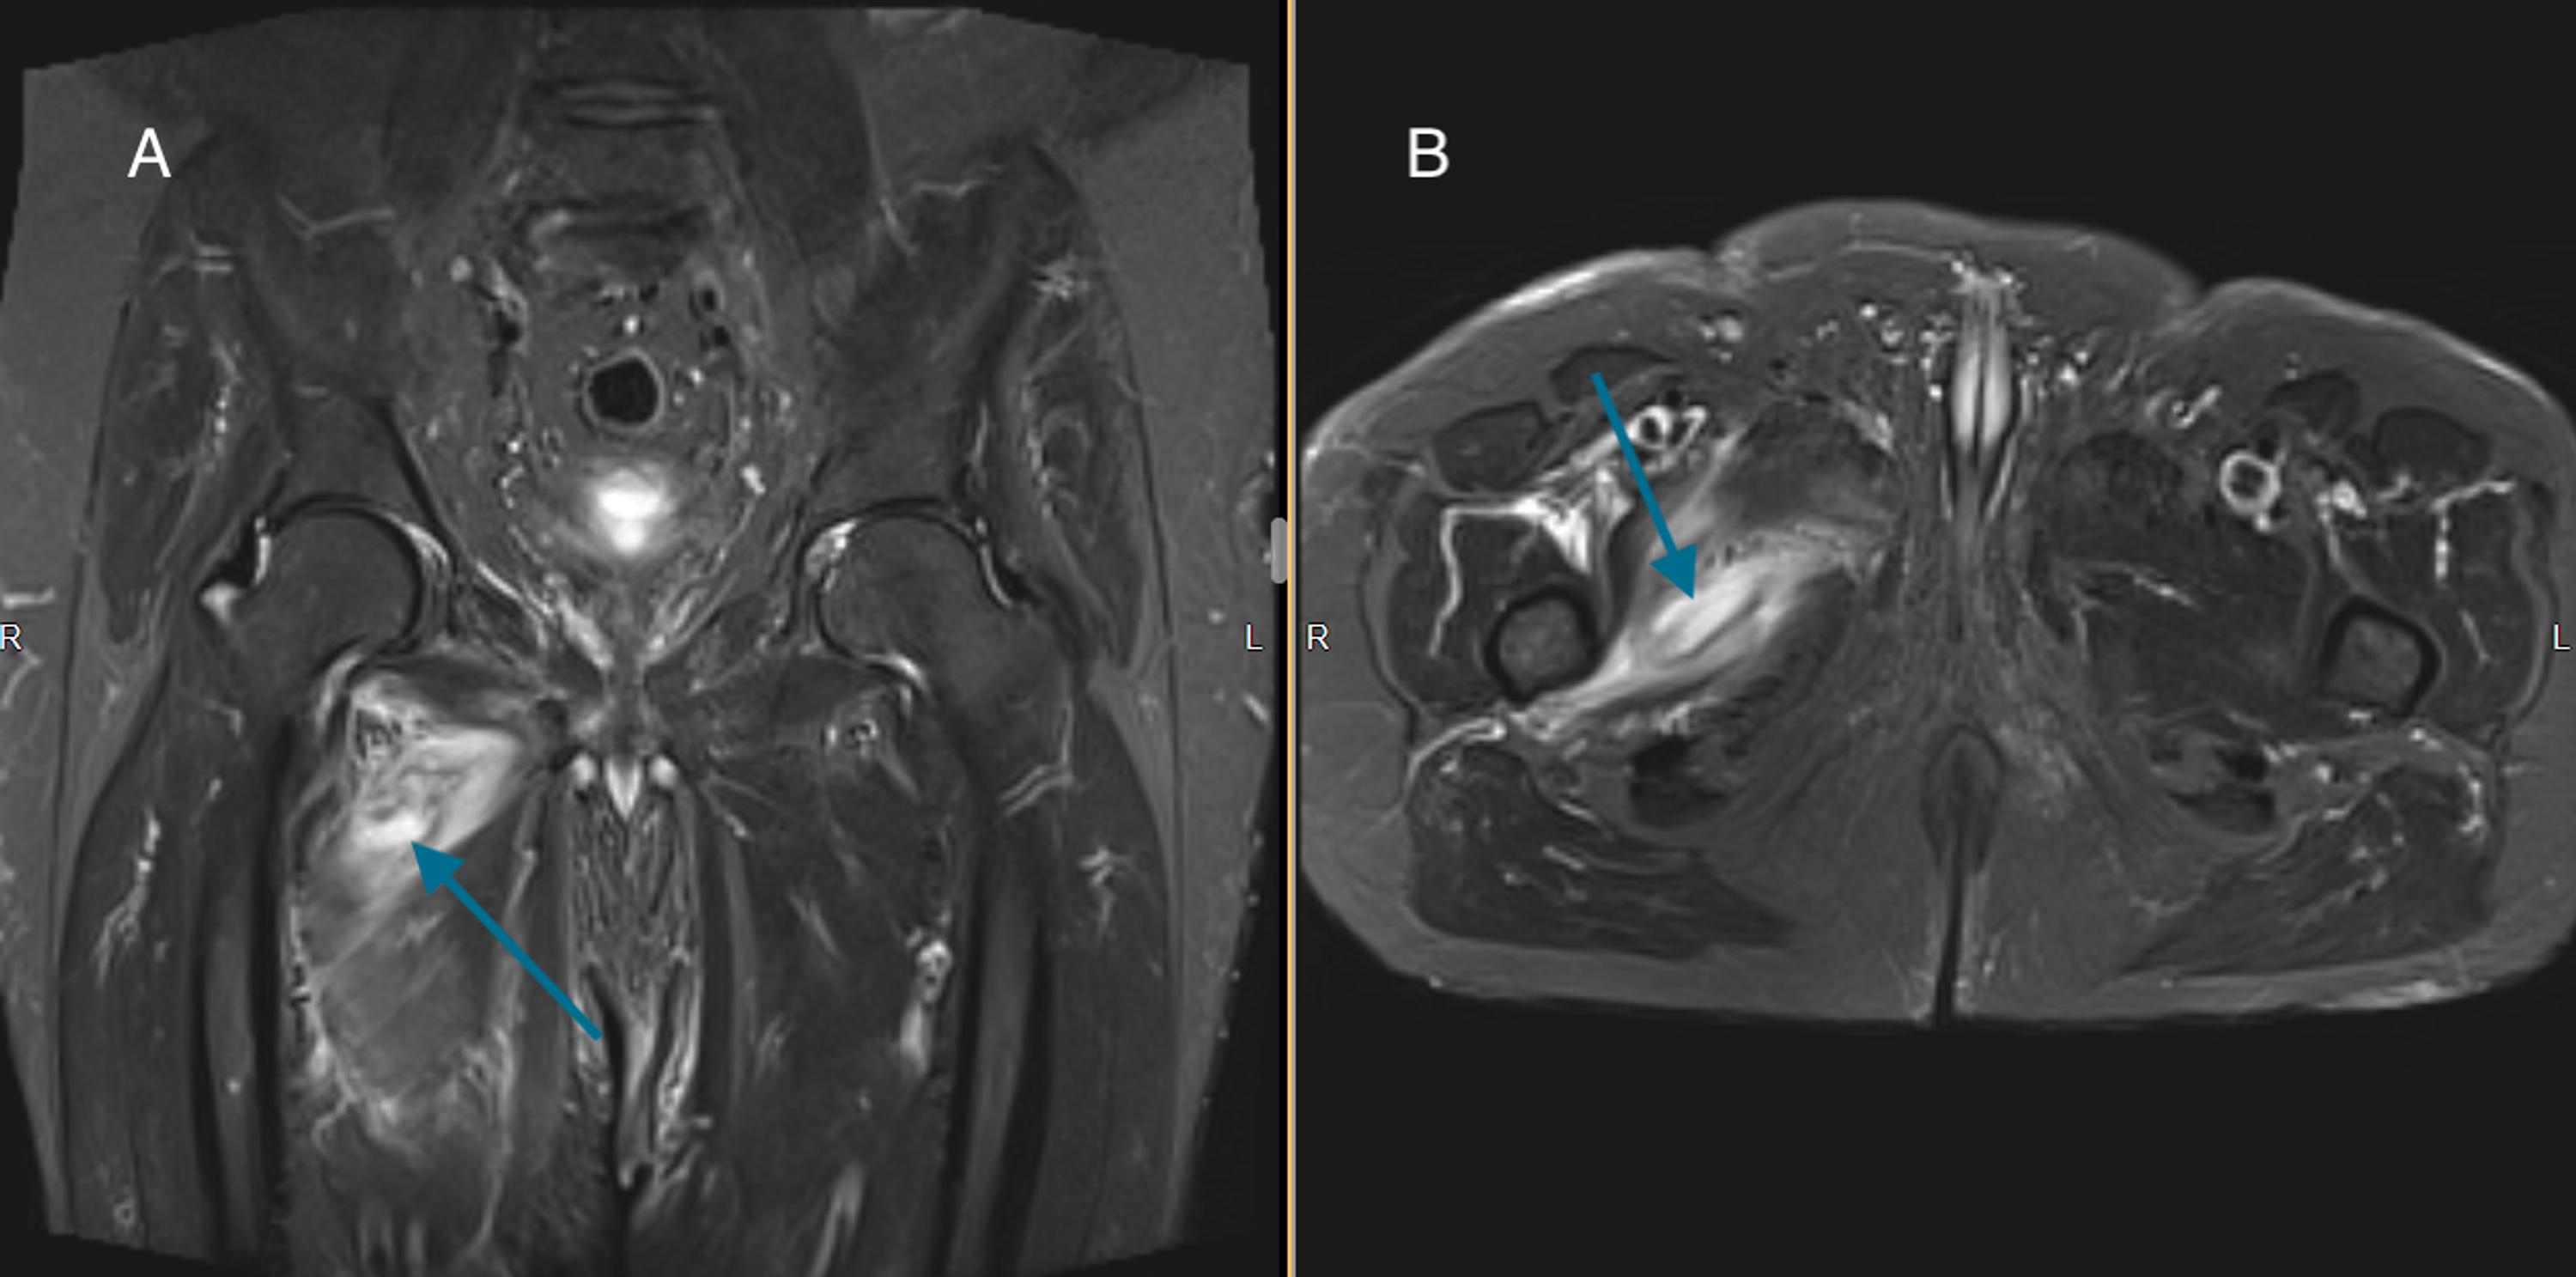

From www.researchgate.net

Hip abductor damage on MRI. Shown is the coronal T1weighted MRimage at Hip Abductor Tear hip abductor or gluteal tendon tears are a commonly missed source of hip pain. Many of these tears often go. learn about the causes, symptoms, diagnosis and treatment of hip abductor tendon tears, a common injury in runners and athletes. hip abductor muscle atrophy, defined as 25% gross muscle wasting seen on mri, was found more frequently. Hip Abductor Tear.